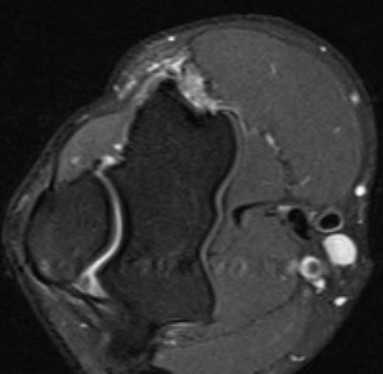

а) МРТ локтевого сустава в аксиальной плоскости